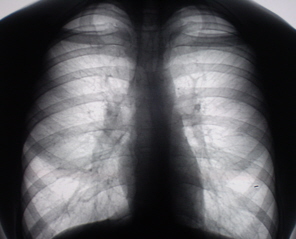

Цифровое стандартное флюорографическое профилактическое исследование (проведено на цифровом флюорографе «Ренекс – Флюоро»). На цифровых флюорограммах, произведенных в прямой, правой и левой боковых проекциях с обеих сторон определяется синдром двусторонней аденопатии. С обеих сторон определяется резкое увеличение и гомгенизация тени корней за счет резко гиперплазированных, в основном, бронхопульмональных лимфатических узлов с довольно чёткими, ровными контурами. Структура тени однородная. На фоне гиперплазированных лимфатических узлов чётко дифференцируются просветы главных бронхов.

Иллюстрации 1, 2, 3.

«Поднят архив». Пациент «проходил» флюорографию в 2007 году два раза – первый в январе, как «профилактическую», в июле месяце – при поступлении на работу. Флюорограммы представлены в виде иллюстраций 4, 5.

Рентгенологическое исследование, выполненное в апреле месяце 2008 г. выявило в грудной полости двустороннюю аденопатию за счет гиперплазии бронхо – пуцльмональных лимфатических узлов. Слева в области подмышечного сегмента нежное снижение прозрачности легочной ткани по типу «нежного пневмонита». Рентгенологических данных за объёмный процесс и полостное образование не выявлено. Выявлены изменения в крестце.